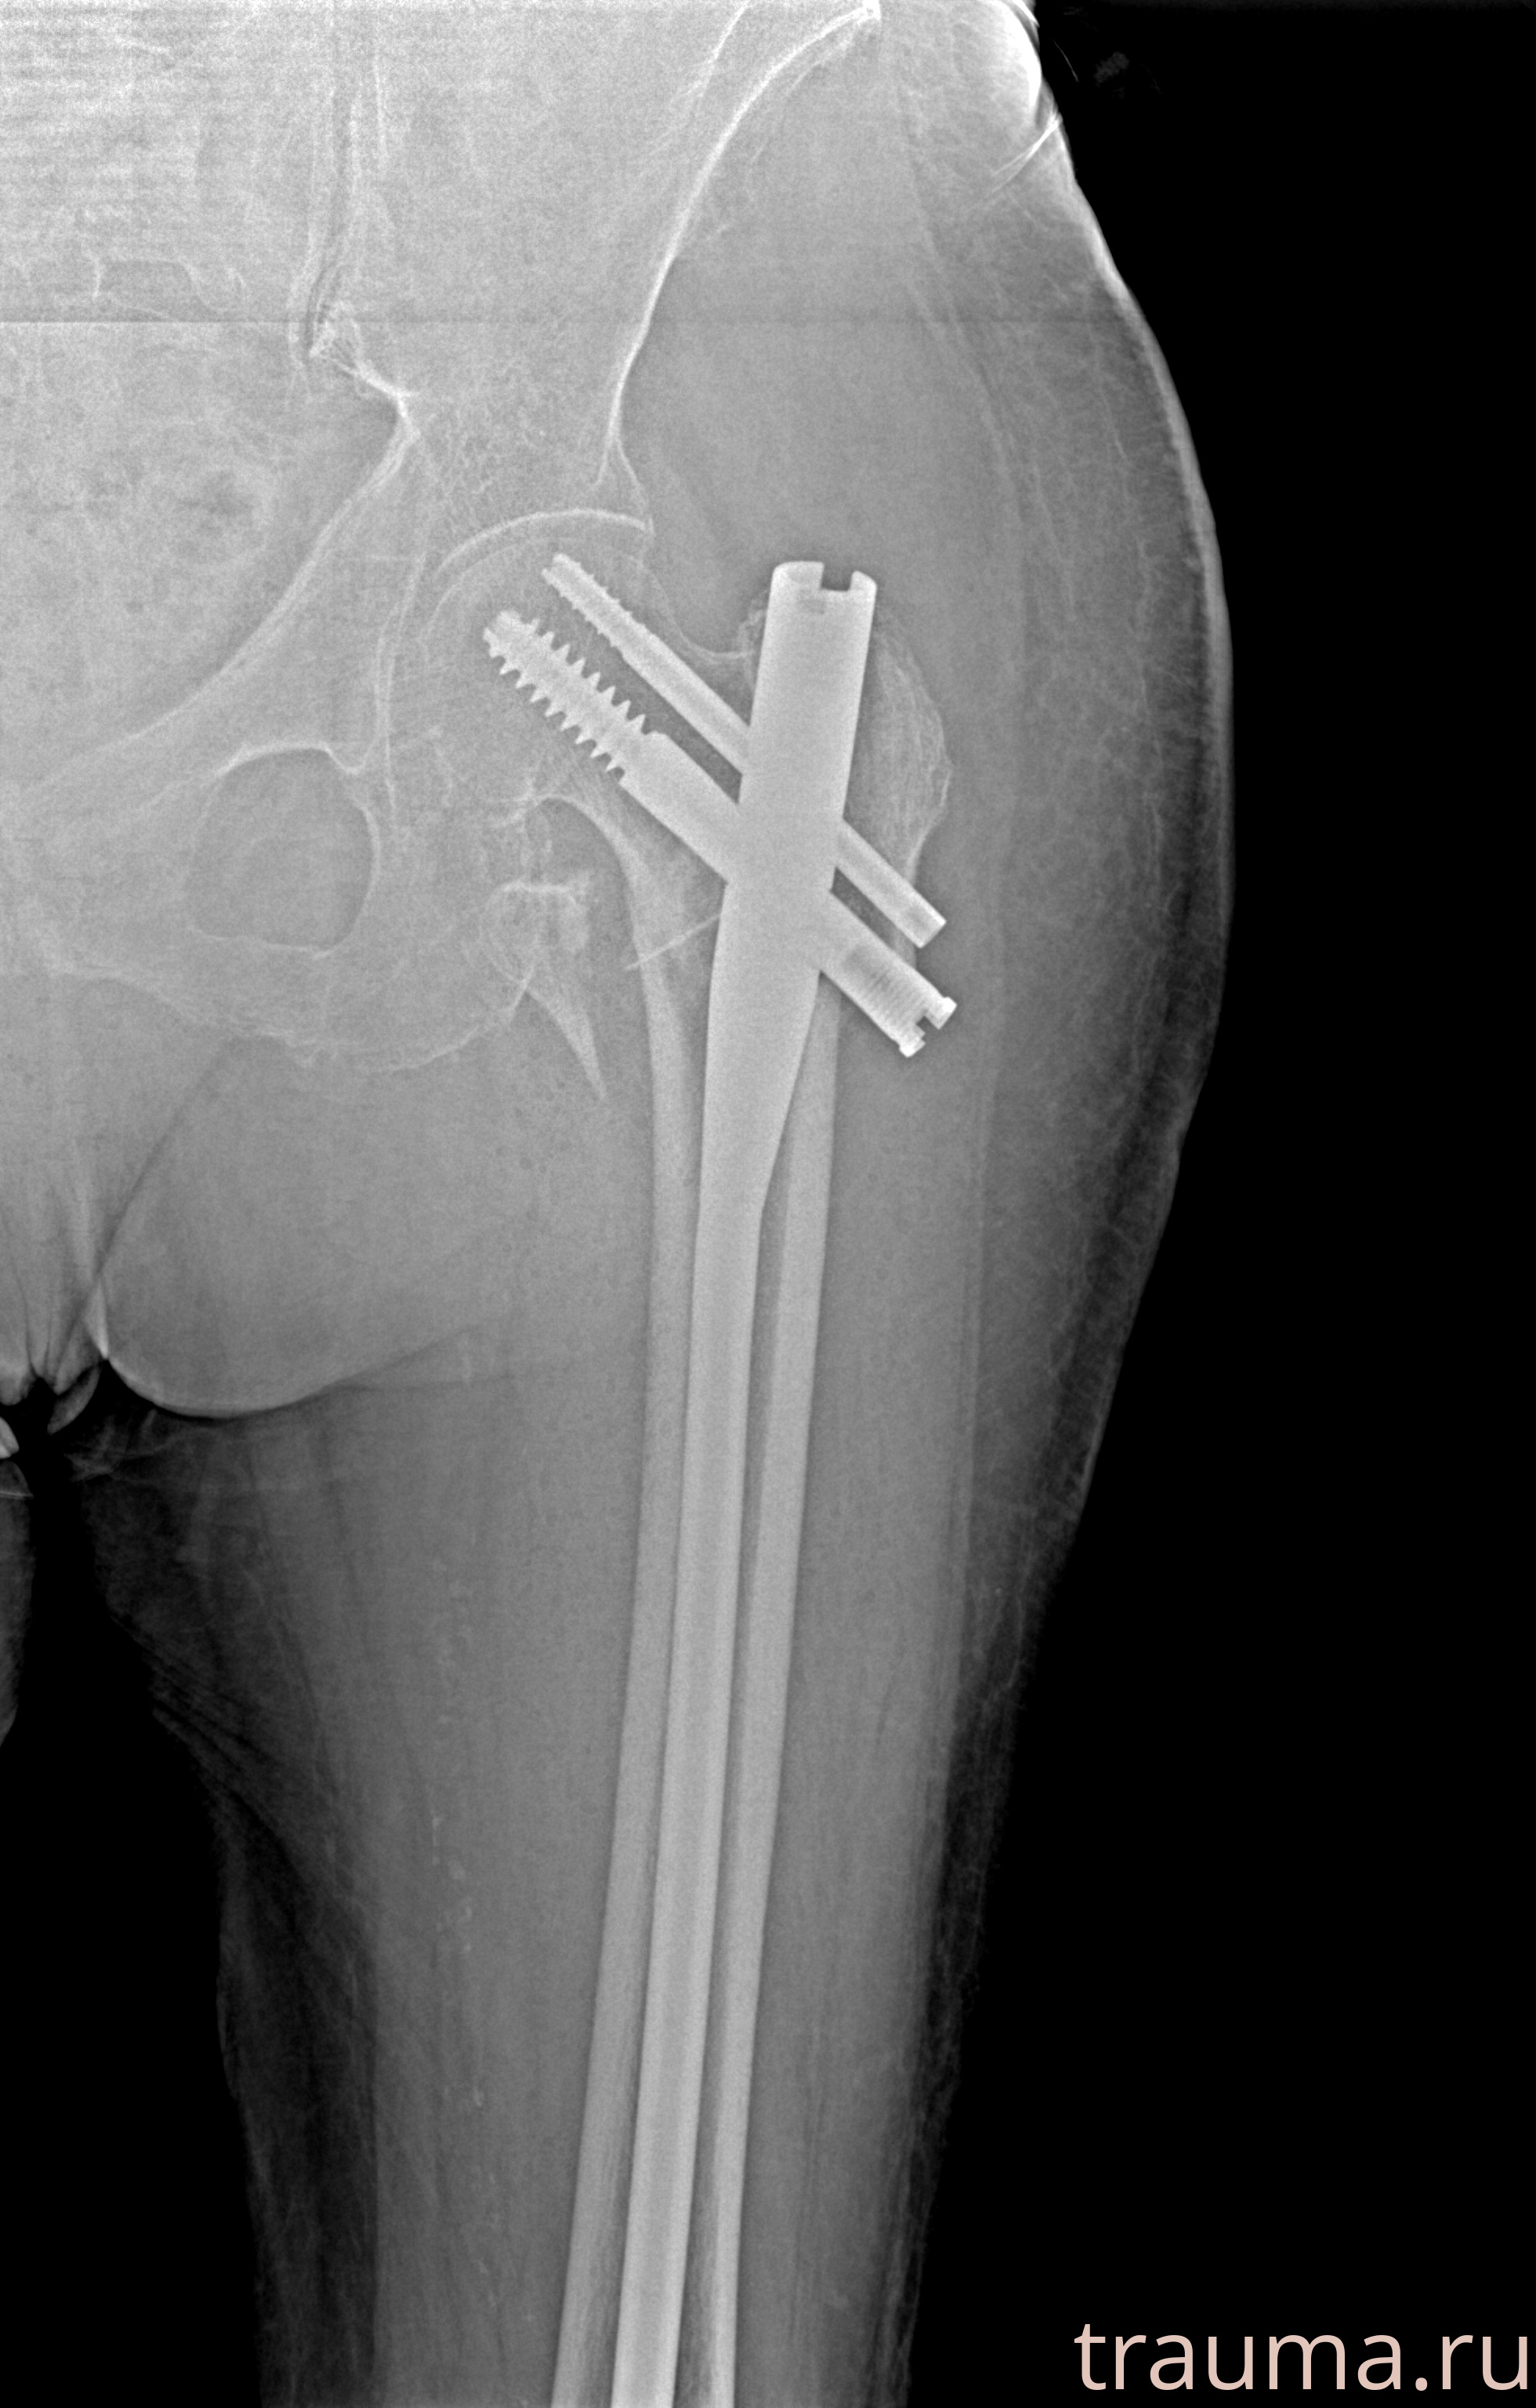

Рентгенограммы

Рентген на дому: по вашему адресу приезжает врач-рентгенолог, травматолог-ортопед с мобильным рентгеновским аппаратом, проводит диагностику травмы или заболевания, делает необходимые рентгенограммы, дает рекомендации по дальнейшему лечению. Получить качественные снимки в домашних условиях возможно благодаря уникальной методике, разработанной МосРентген Центром для института  Склифосовского

при переломе шейки бедра и пневмонии от компании МосРентген Центр - партнера Института имени Склифосовского